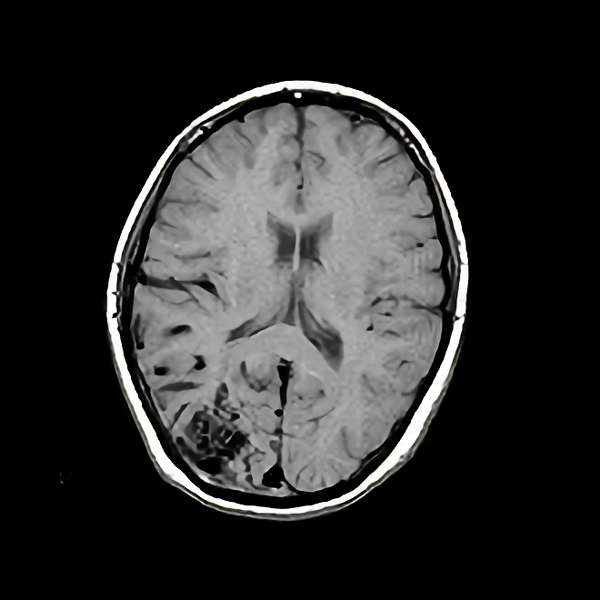

No.452 手術後